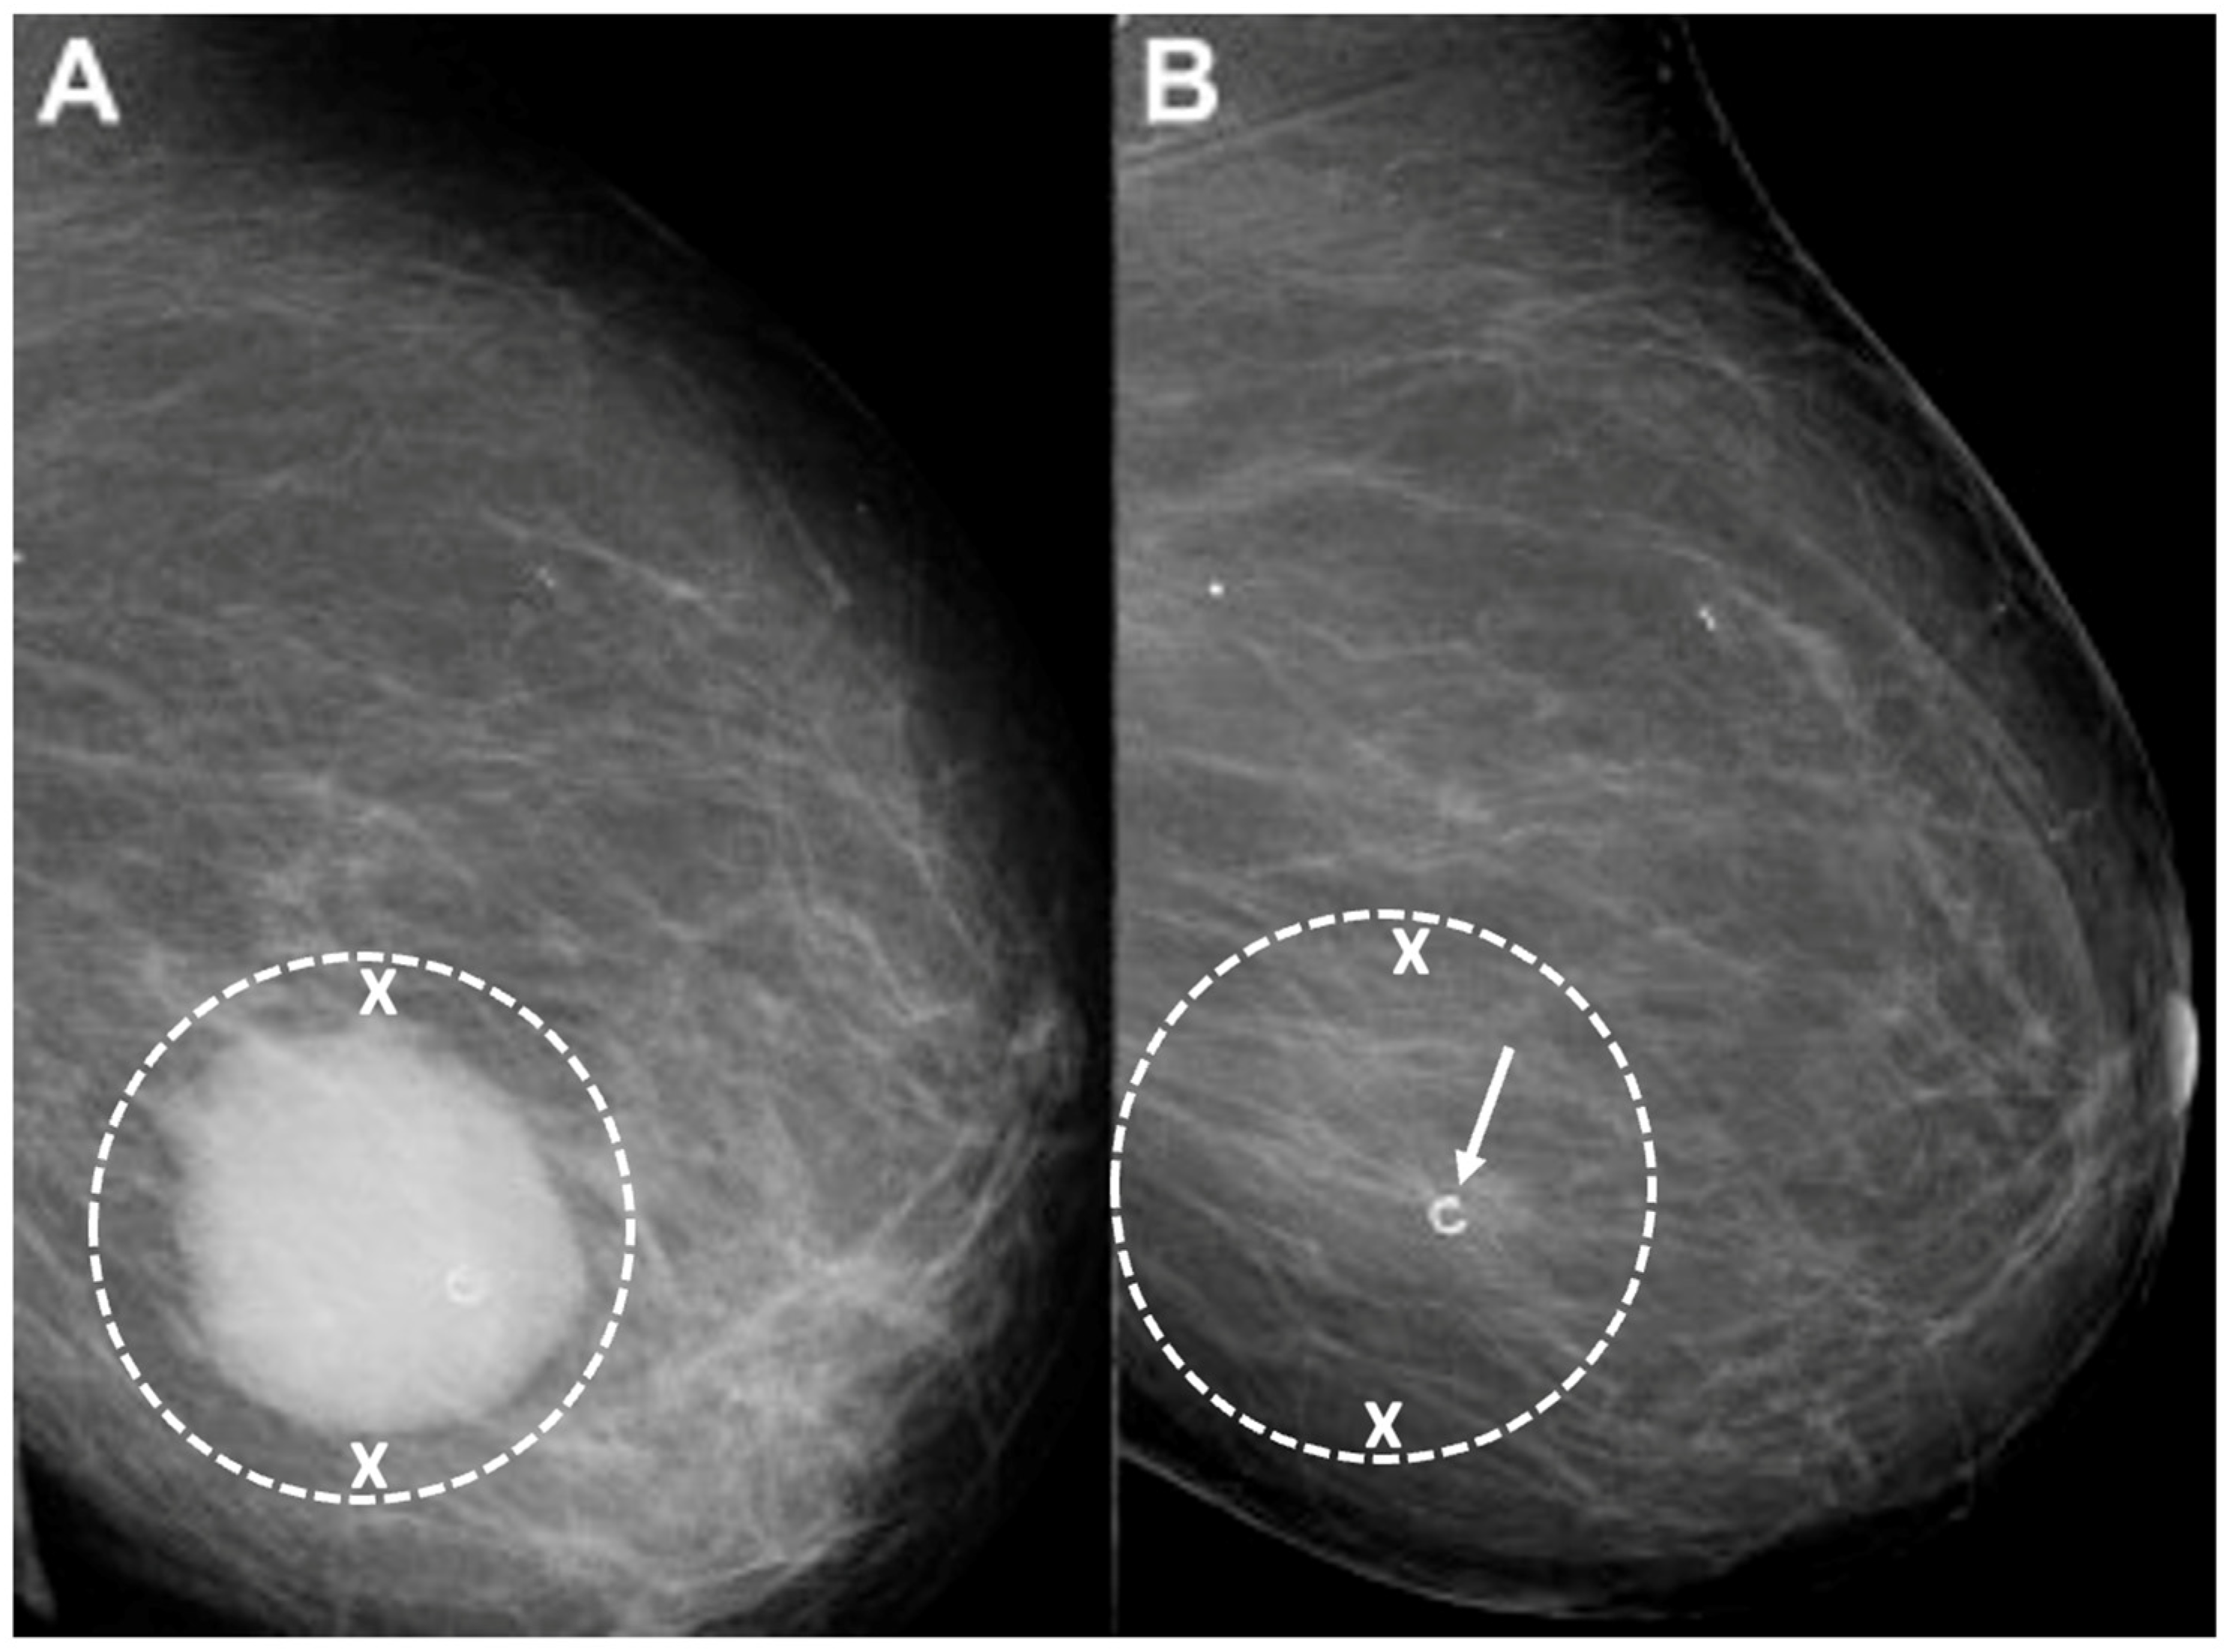

Digital Mammography. Breast cancer staging should include bilateral digital diagnostic mammograms (preferably 3D mammograms or tomosynthesis) to evaluate the extent of disease. Although cryoablation is generally performed under ultrasound or CT-scan guidance, high-quality mammography might reveal additional areas of cancer in the same region of the breast (multifocal cancer) or in a different region of the breast (multicentric cancer) that might impact patient selection or alter the cryoablation treatment plan. Multicentric and multifocal breast cancer is generally regarded as a contraindication to cryoablation. Pre-treatment assessment of the mammograms should seek the detection of spiculations (radial tumor extensions) and/or microcalcifications that might reach beyond the main tumor mass and require incorporation in the cryoablation treatment zone (Figure 1). Since mammography is the only imaging study that reliably shows microcalcifications, mammography plays a particularly important role in determining disease extent when suspicious microcalcifications are part of the disease process. Consequently, patients who are generally opposed to obtaining screening mammograms should be encouraged to have at least one set of pre-treatment diagnostic mammograms to exclude the presence of suspicious microcalcifications that could impact patient selection and/or treatment planning.

Figure 1.

Mammogram showing density corresponding to a palpable mass (see dashed lines) as well as suspicious microcalcifications (arrows) and inset image showing magnified view of white punctate calcifications extending beyond the palpable mass.